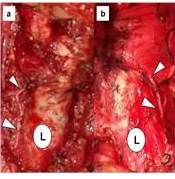

La herida quirúrgica vino determinada por el tipo de procedimiento. En las lobectomías tiroideas y las tiroidectomías totales se ejecutó el trazo de Kocher. En caso de requerir linfadenectomía cervical lateral se realizó la incisión en “J”, conocida también como en “Palo de Hockey”. La identificación del nervio laríngeo recurrente se inició en todos los casos por encima del desfiladero torácico y se siguió en dirección cefálica hasta la laringe. En ocasiones se intentó el reconocimiento en la articulación cricotiroidea, por donde ingresa en la laringe (Figura 1a y b).

Un cuarto de la serie presentó divisiones extra-laríngeas del nervio laríngeo inferior, predominando la bifurcación en dos ramas, en tres ramas y una de seis ramas (Figuras 3 a-d y 4 a-c). En un paciente se constató la presencia de una conexión entre un ramo nervioso superior y el nervio laríngeo recurrente en el sitio de entrada en la articulación cricotiroidea (Figura 4d). Un cuarto de la casuística desarrolló disfonía, una fue permanente.